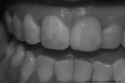

Cuando hablamos de estética no solo hablamos de belleza y armonía en las piezas dentales, sino de algo aún más importante: NATURALIDAD, tres conceptos íntimamente ligados.